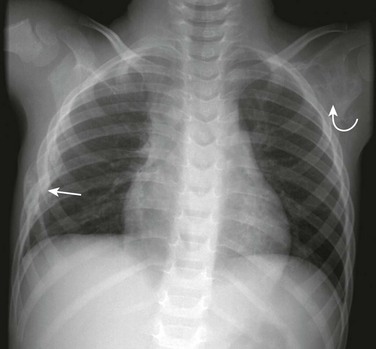

e-Figure 59-5 Cleidocranial dysostosis in an adolescent boy.

A chest and abdominal radiograph shows absence of the right clavicle and hypoplasia of the distal half of the left clavicle (curved arrow). Diastases (straight arrow) of the symphysis pubis also is present. The patient has scoliosis and is wearing a brace.